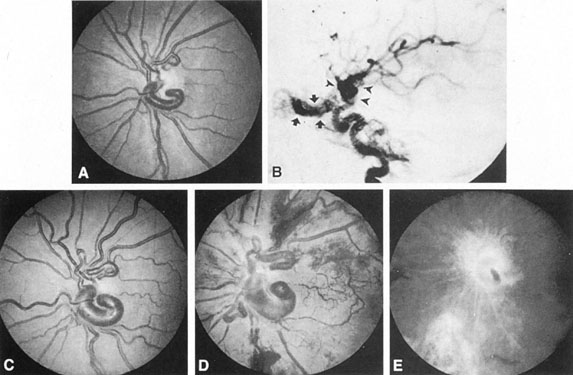

Fig. 7. Supratentorial arteriovenous malformation in a 28-year-old woman with a history of focal motor seizures for many years and a recent subarachnoid hemorrhage. A: Lateral projection carotid arteriogram demonstrating a huge deep hemispheral arteriovenous malformation. B: Frontal projection. C: Fundus photograph showing anomalous tortuous vasculature in each eye. No retinal arteriovenous shunt was detectable.

Fig. 8. Multiple supratentorial arteriovenous malformations (AVMs). A: Lateral projection of left carotid arteriogram shows dilated afferent artery (solid arrow) feeding the right hemispheric parietal AVM (open arrow). B: Right carotid injection fills a second, more posteriorly located, parietooccipital AVM (open arrow), which drains immediately to markedly dilated cortical veins (curved arrow).

In general, when hemorrhage occurs involving a portion of the visual radiations, a homonymous visual field defect is to be expected. Selective involvement of the anterior visual pathways may occur either with extensive venous angiomas at the base of the brain or as part of the Wyburn-Mason syndrome (see later), with direct involvement of the optic nerve, chiasm, or tract. Other variants such as congenital cavernous hemangiomas may involve the anterior visual pathways,68 as may intraparenchymal cryptic AVMs69 and present as symptomatic visual loss also resulting from hemorrhage and hematoma. Amaurosis fugax may even be the presenting symptom of supratentorial AVMs when blood is shunted to the meningeal circulation from the ophthalmic artery.70 When supratentorial AVMs drain into dural venous sinuses or the vein of Galen, distant ocular effects evolve, such as proptosis71 or ophthalmoplegia72 because of arterialization of cavernous sinus complex.

Of particular interest are those AVMs that involve the occipital lobe (Fig. 9). The clinical differentiation of migraine from a cerebral AVM was previously regarded as difficult because the clinical features of occipital lobe AVMs include visual phenomena or headaches. However, in most cases the clinical distinction is possible. In 26 cases with occipital AVM, two distinct syndromes were defined in 18 patients: occipital epilepsy and occipital apoplexy.73 Focal seizures with occipital malformations consist of elementary visual sensations similar to the phenomena evoked by direct cortical stimulations. When seizure activity occurs in the striate cortex (area 17), the patient usually reports sensations of moving lights in the right or left homonymous fields. The sensations are poorly formed, episodic, usually brief, sometimes colored, and unassociated with the angular, scintillating figures so characteristic of migrainous cortical phenomena. Epileptic discharges from areas 18 and 19 cause photopsias that are unlikely to remain stationary and to flicker rapidly. The epileptic photopsias usually last only seconds; occasionally they last for a few minutes before the onset of a generalized seizure. In other instances only the brief visual episodes occur without spreading to produce a generalized seizure. Momentary dimming or blindness in one or both homonymous fields may be experienced with seizure activity in the occipital areas.

Fig. 9. Carotid arteriogram of an occipital lobe arteriovenous malformation (AVM). Lateral (A) and frontal (B) projections demonstrating a small occipital AVM (arrow). The patient was a 23-year-old woman who presented with severe apoplectic unilateral headache, total left homonymous hemianopia, and mild nuchal rigidity. Despite xanthochromic cerebrospinal fluid, she was initially diagnosed elsewhere as having migraine. An AVM was successfully resected, and a small occipital lobe hematoma was removed.